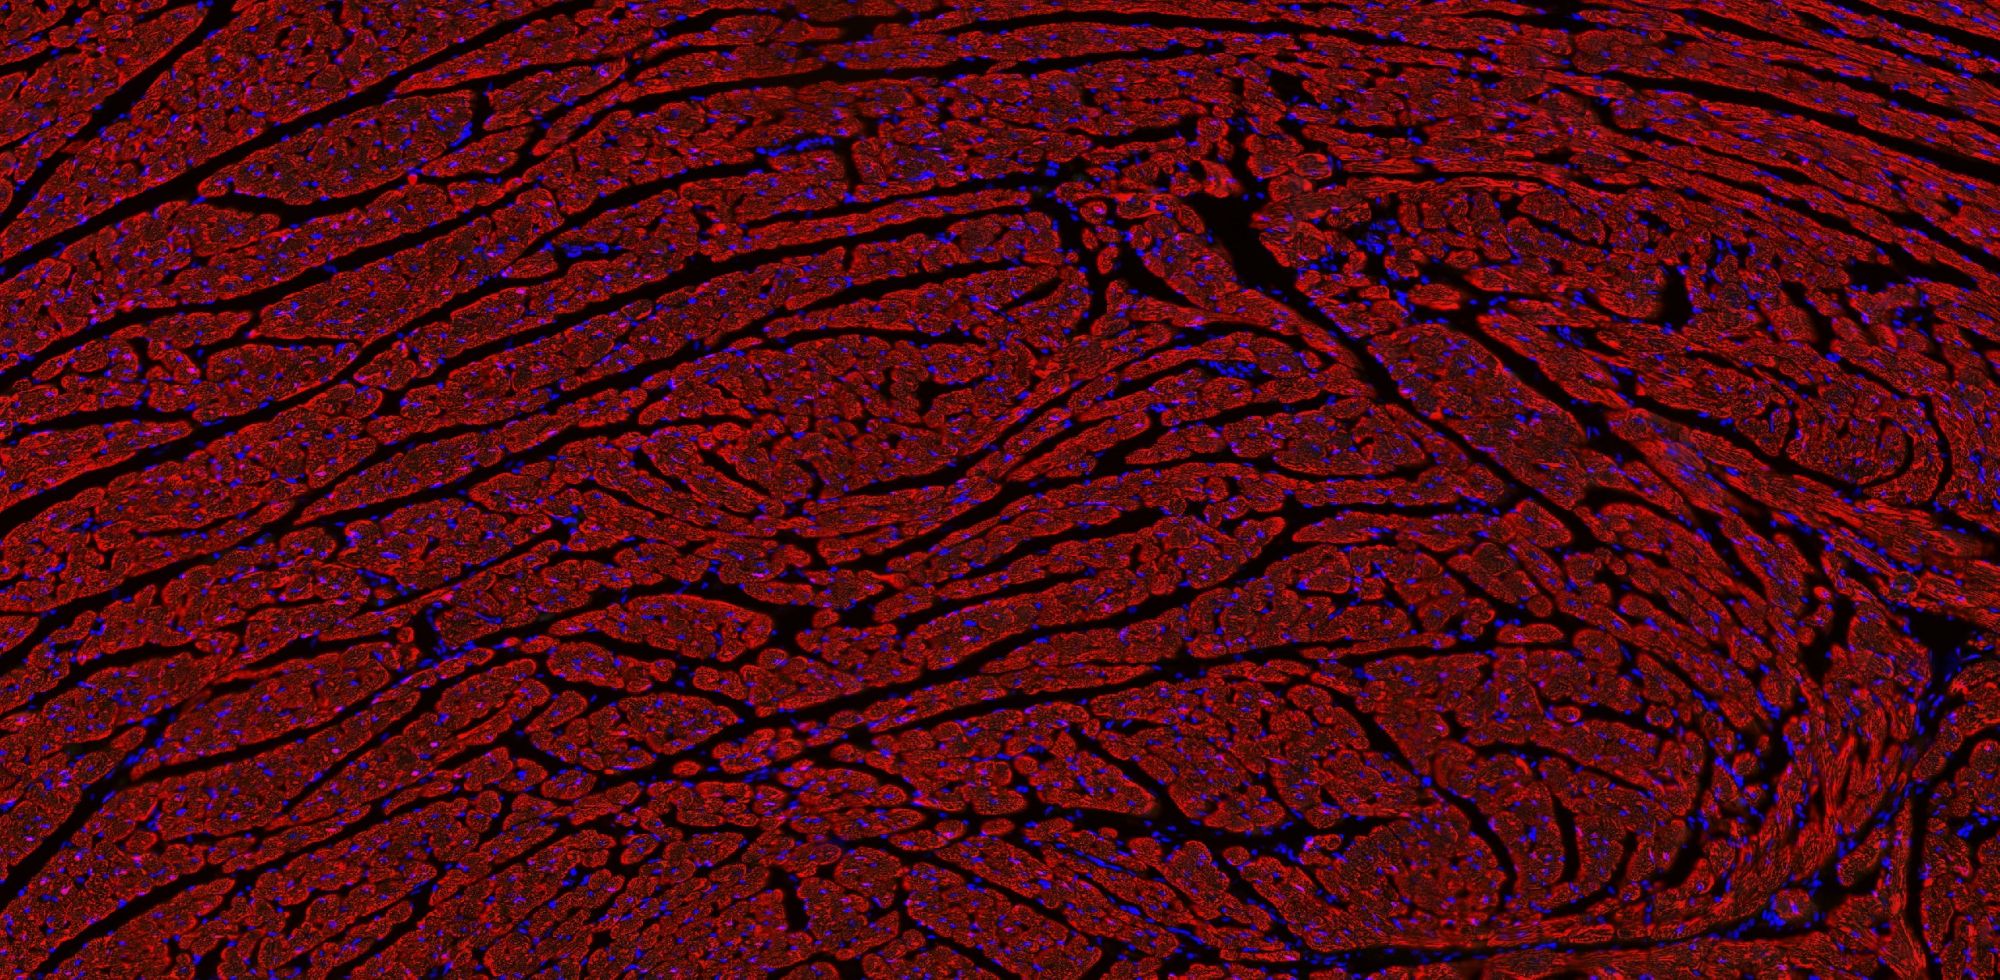

免疫學的基本反應是抗原-抗體反應。由于抗原抗體反應具有高度的特異性,所以當抗原抗體發(fā)生反應時,只要知道其中的一個因素,就可以查出另一個因素。免疫熒光技術(shù)就是將不影響抗原抗體活性的熒光色素標記在抗體(或抗原)上,與其相應的抗原(或抗體)結(jié)合后,在熒光顯微鏡下呈現(xiàn)一種特異性熒光反應。